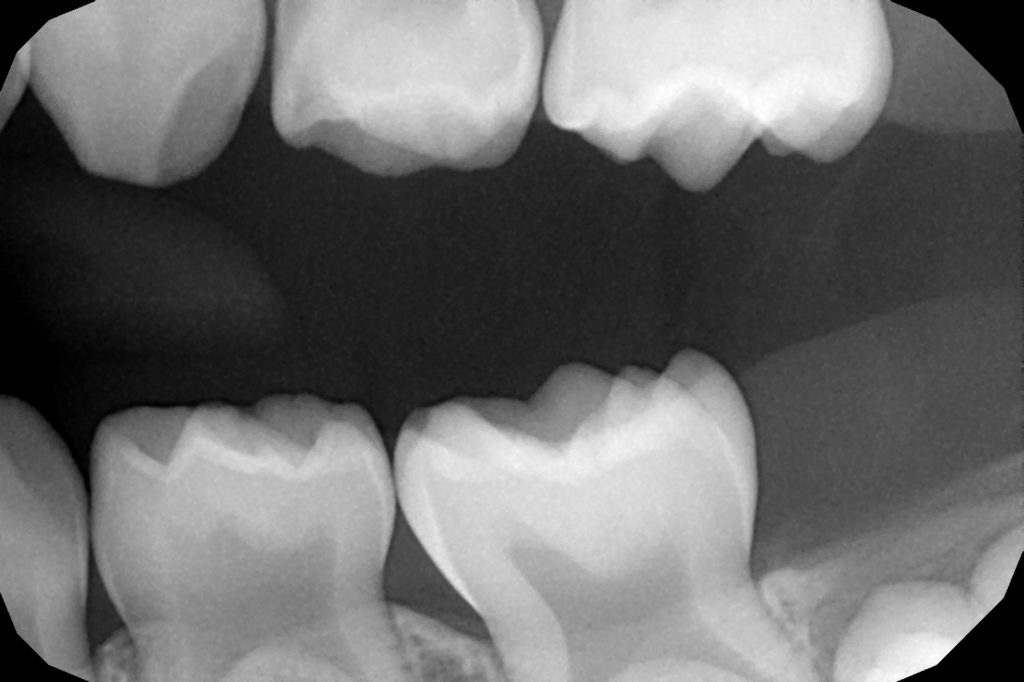

From decisionsindentistry.com